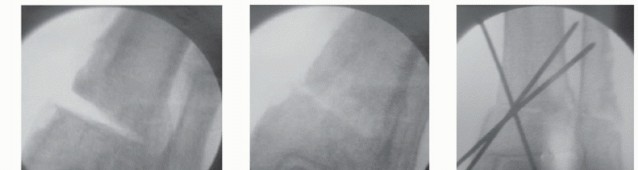

TECH FIG 1 • Medial closing wedge supramalleolar osteotomy. A. Using a preoperative radiograph, the center of rotation of angulation (CORA) is located at the intersection of two lines that represent the mechanical axes of the proximal and distal segments. B. Under fluoroscopy, a Kirschner wire is inserted to the tibia perpendicular to the mechanical axis and a second Kirschner wire is inserted parallel to the ankle joint line intersecting the first wire, ideally at the apex of the deformity. C,D. Guide pin wires used to perform a closing medial wedge osteotomy. Pin A has been inserted to the tibia perpendicular to the mechanical axis and pin B has been inserted parallel to the ankle joint line, intersecting pin A at the apex of the deformity. E. The cut wedge. The pins have been used as a guide for the tibial cuts, whereas the size of the wedge has been determined during the preoperative planning. (continued)

- TECH FIG 1 • (continued) F. Fluoroscopic view of the resected wedge. G. Fluoroscopic view of the closed osteotomy. H,I. Fluoroscopic AP and lateral views of the provisionally fixed osteotomy with Kirschner wires. J. Photo of the applied periarticular plate. Note the excellent fit on the distal tibia. K. The applied periarticular plate after completion of fixation with three screws in the distal segment. L. Fluoroscopic view of the osteotomy after completion of fixation.

We routinely use Kirschner wires to define our proposed osteotomy; for an opening wedge osteotomy, we use a single Kirschner wire, but for the medial closing wedge osteotomy, two Kirschner wires are required to define the tibial wedge resection. Under fluoroscopic guidance, insert the first Kirschner wire perpendicular to the mechanical axis and the second parallel to the ankle joint, intersecting the first Kirschner wire at the apex of the deformity. The size of the wedge has been determined during the preoperative planning, and the Kirschner wires are positioned 1 to 2 mm wider than the proposed osteotomy, so they can be left in place as a guide for the saw cuts. Although the Kirschner wires define the osteotomy in one plane, the surgeon must also orient the saw blade perpendicular to the tibial shaft axis when performing the osteotomy. With the anterior and posterior soft tissue and neurovascular structures protected, we routinely use a broad oscillating saw, constantly irrigating the blade with cooled

sterile saline or water to limit osteonecrosis. Ideally, a thin cortical bridge and periosteal sleeve on the opposite cortex will be preserved to allow for a greenstick-like closure of the osteotomy that facilitates maintenance of alignment and enhances stability. However, when the osteotomy is intentionally performed at a level different than that of CORA, then the opposite cortex must be violated to allow the distal segment to be translated.

After removing the resected wedge and performing appropriate translation of the distal segment, close the osteotomy and provisionally fix it with Kirschner wires. The provisional fixation may be guidewires for intended cannulated screws or it must be positioned so as not to interfere with the definitive fixation.

Assess alignment of the tibia and ankle fluoroscopically, both in the AP and lateral planes.